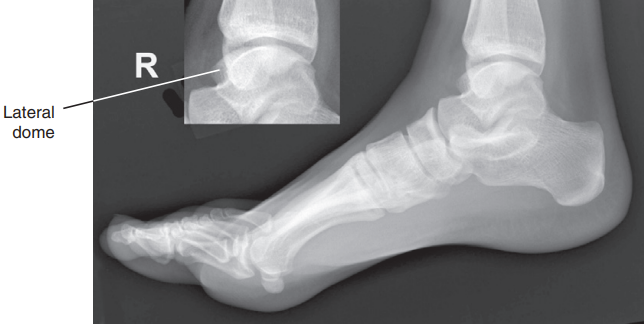

What are the issues with this ankle?

Foot is not dorsiflexed

the medial talar dome is demonstrated posterior to the lateral talar dome and the fibula will be demonstrated more anteriorly on the tibia

Internal rotation

the medial talar dome is demonstrated anterior to the lateral talar dome and the fibula is more posterior on the tibia

External rotation

The lateral talar dome is proximal to the medial dome, the height of the medial longitudinal arch appears less than it actually is, and the talocalcaneal joint is narrowed.

Proximal lower leg has been elevated